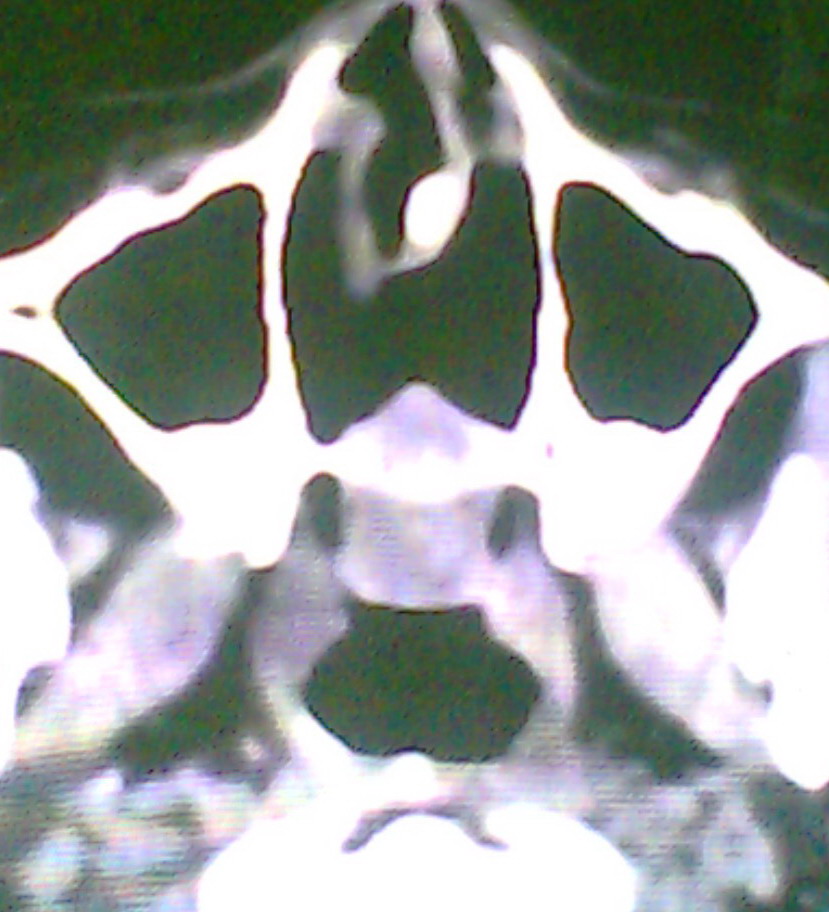

女、18岁,身高1.5左右,鼻塞、流涕数月,两侧瞳孔明显增大,曾与几年前去北京看眼,未发现病变。

是囊肿吧?怎么没有骨窗呢

建议冠状面扫描,支持:脑膜鼻内膨出; 蝶窦粘液囊肿突入鼻腔可能性小。

像这种病人应常规加扫冠状位扫描;

在上级医院冠状位ct扫描后,诊断为:脑膜膨出,已住院准备手术。等待术后结果。